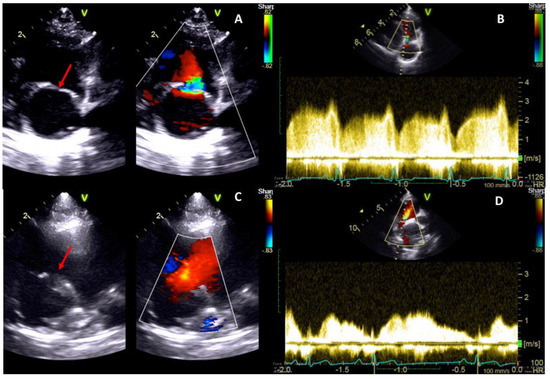

2.1. Case 1

2.2. Case 2

| Before the Procedure | After the Procedure | |

|---|---|---|

| Membrane’s orifice (mm) | 3 | 10 |

| Diameter CaVC (mm) | 14.4 | 12.0 |

| CaRA (mm) | 23.1 | 15.5 |

| CrRA (mm) | 24.8 | 24.8 |

| Tricuspid annulus (mm) | 22.1 | 22.1 |

| Transmembrane Vmax (m/s) | 3 | 1.2 |